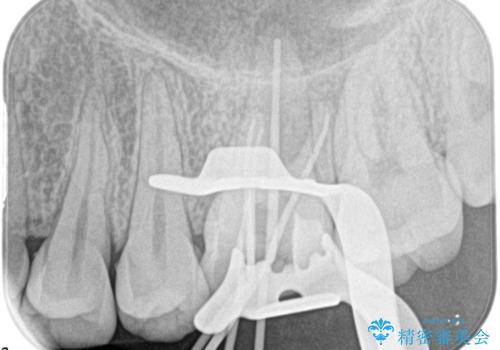

奥歯の根管治療

- 定期検診にて根尖に病変を認めた患者様です。

歯髄壊死の診断にて根管治療を行っております。

- 精密根管治療(イニシャルケース,大臼歯):122,000円、ファイバーコア:22,000円費用は治療当時の料金となります